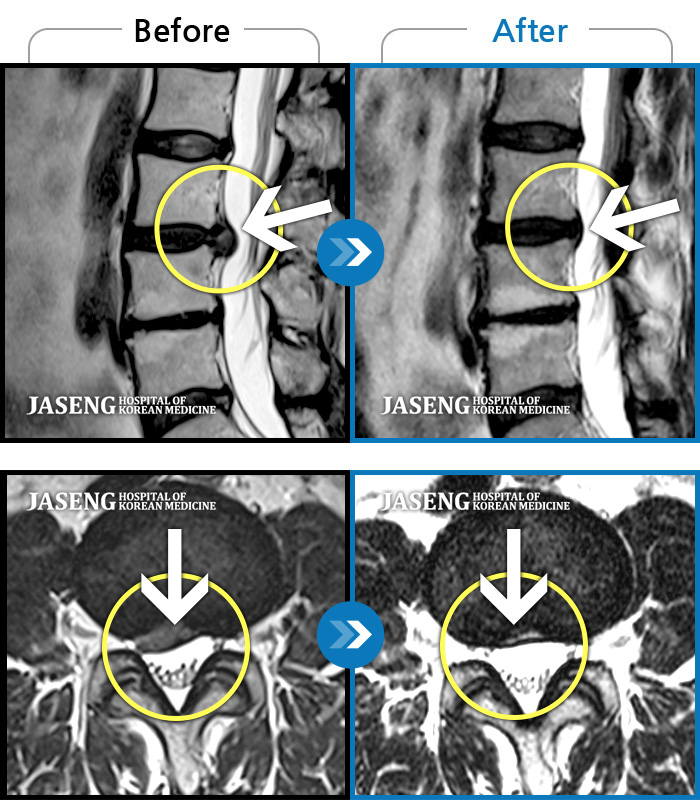

Before

After

허리통증, 왼쪽 다리 저림 및 통증

2018.01.18 ~ 2019.08.09